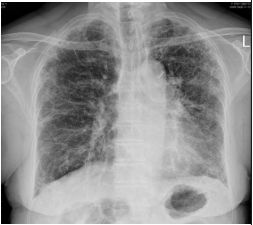

8. 68歲男性主訴慢性咳和喘,胸部X光如圖,下列何種影像檢查最有助於診斷? (A) 胸部磁振造影(MRI) (B) 超音波掃描 (C) 注射顯影劑之胸部電腦斷層 (D) 高解析度之胸部電腦斷層 (E) 正子電腦斷層(PET-CT)